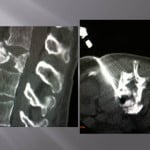

Vertebroplasty technique in the burst fracture of A2 type in the Magerl classification (split-burst fracture)

Vertebroplasty in the split-burst fracture is a delicate intervention for numerous reasons. The fracture separates the vertebral body into two parts with a possible recess of the posterior wall. This intervention stays in the limits of the indications of vertebroplasty, it must be decided in conjunction with the neurosurgical or orthopedic team.

Numerous publications show the efficacy of this procedure (amoretti, huet) and the small rate of complication. In our experience, the coupling of scopy and scanner is fundamental. The axial cuts allow for visualization of the extremities.

The progression of trocars is done successively by controlling the scanners and lateral scopies. We use 13 gauges trocars, the penetration is performed manually, we avoid using a surgical hammer to limit he risks of displacements of bone fragments. We **transfixions the fractured centre with the two trocars bilaterally and symmetrically. , their ends being located medially to limit lateral leaks.

The cement is injected at the level of the anterior fragment of the fracture at its paste phase, then the trocars are slowly withdrawn at the level of the fracture while injecting progressively the cement and create a cement bridge with the anterior fragment and the fracture trait. A scanner control verifies that the end of the trocars is located perfectly in the fracture. The cement is injected slowly in the cannula and pushes with the needle of the trocar.

The lateral scopy controls real time diffusion of the cement in the fracture. The axial scannographic cuts confirm the correct diffusion in the fracture and the absence of para-vertebral leaks. The trocars are progressively withdrawn while injecting cement in the cannula with a needle. Standing up is authorized the day after with wearing corset. The clinical and radiological follow up is rigorous to avoid detecting all neurological sign of compression and appreciate the vertebral consolidation.